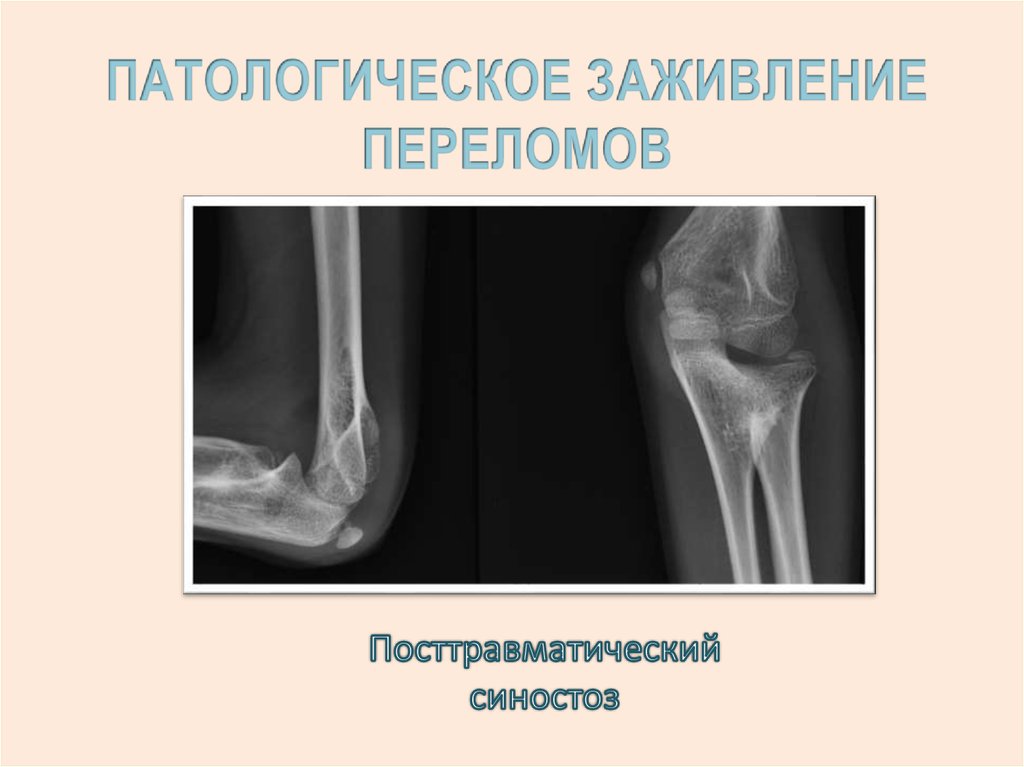

12.

13.

14.